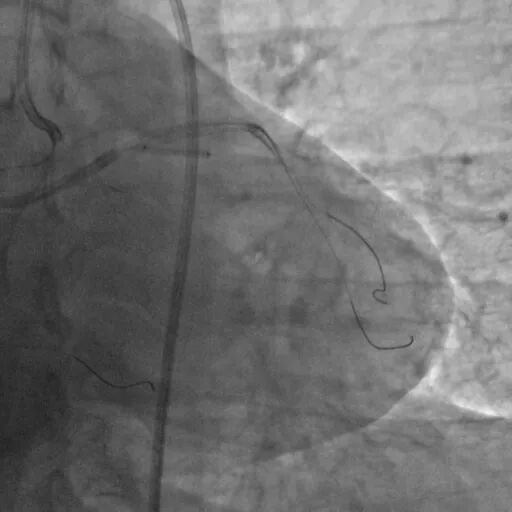

直接尝试逆向,RCA中段3.0*10切割后,使用Finecross150+SUOH03通过心外膜逆向进入LAD,FC轻松跟进。

使用P200导丝攻击远端纤维帽前进困难,更换G3进入LAD近段内膜下,直接使用Telescope™导引延长导管辅助下AGT技术,r-CART后G3顺利进入Telescope™导引延长导管。

直接使用G3导丝rendezvous,球囊扩张后行IVUS检查确定血管直径及支架落脚点。

D1释放DCB,LAD植入支架后D1血流影响,工作导丝找回后使用球囊扩张并kissing。

造影发现LAD远端病变仍较重,释放DCB。

复查造影并行ivus检查 支架贴壁良好 无累及夹层。

RCA中段扩张后出现夹层,植入DES。